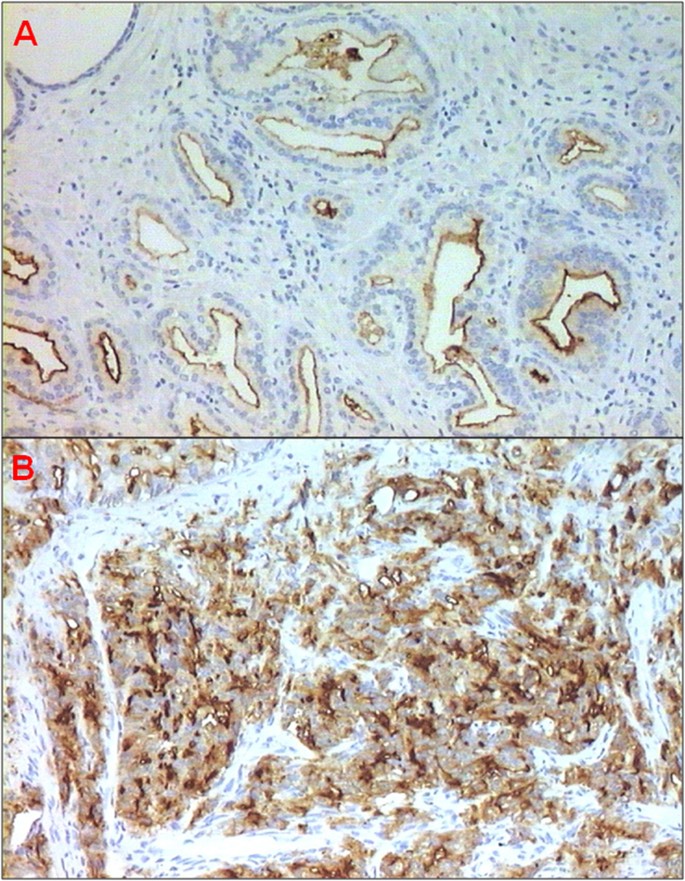

PSMA-positive PCa. (A) GS 6 (3 + 3, Grade Group 1) prostate adenocarcinoma (10 × magnification) with moderate endoluminal membrane staining. (B) GS 8 (4 + 4, Grade Group 4) prostate adenocarcinoma (10 × magnification) with strong membrane staining.

Table 4 reports median PSMA expression values in the different Gleason patterns according to cellular morphology and differentiation. Lower expression of PSMA was observed in Gleason pattern 3 with respect to Gleason patterns 4 and 5, both of which showed higher PSMA expression (P < 0.0001) (Table 4). Absent or weak PSMA expression was observed in the normal and benign tissue analyzed (Table 4). In addition, stronger PSMA staining intensity was more frequently observed in the less differentiated Gleason patterns 4 and 5 than in Gleason pattern 3 (p < 0.0001) (Table 5).